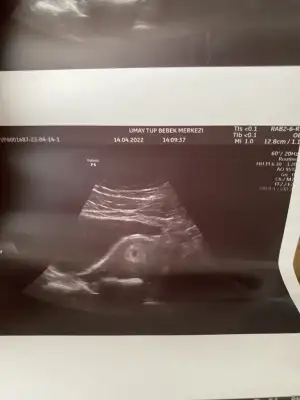

Arkadaşlar Bende kese 4+3te soldaki

5+1 de yani bugün bu şekilde göründü

Biri normal haftasında sanırım 5+1 olan diğeri biraz geride kalmış ama bence korkma zaten ikizlerde hep duyuyoruz ya biri daha iri büyük oluyor diğeri küçük kalıyor bu da onun gibi bence. Ama tabi doktorunuz ve ikiz gebelik geçiren arkadaşlar daha iyi bilir